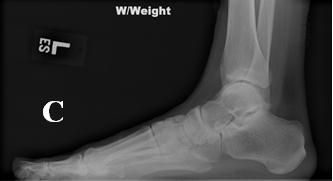

Figure 1C

The patient's normal-appearing left foot radiograph (

C

) is shown in comparison with his right foot radiograph (

D

), which reveals consolidation of the osseous fragments creating the chronic joint subluxation and bony prominence on the bottom of midfoot. Figure 1D

Also seen in Figure 1 are a normal-appearing radiograph of a patient’s left foot and, for comparison, a radiograph of the patient’s right foot showing consolidation of the osseous fragments creating the chronic joint subluxation and bony prominence on the bottom of the midfoot.